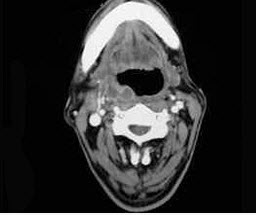

[单选题,B1型题] 如图,出现咽旁脓肿侵犯颈静脉可出现()。A . Horner综合征B . 严重出血C . 张口困难D . 喉痉挛E . 血栓性静脉炎

[单选题,B1型题] 如图,出现咽旁脓肿侵蚀颈动脉可引起()。A . Horner综合征B . 严重出血C . 张口困难D . 喉痉挛E . 血栓性静脉炎

[配伍题,B型题] 出现咽旁脓肿侵蚀颈动脉可引起()一旦咽旁脓肿感染累及翼内肌可引起()如咽旁脓肿侵犯颈交感干可出现()出现咽旁脓肿侵犯颈静脉可出现()A .Horner综合征B .严重出血C .张口困难D .喉痉挛E .血栓性静脉炎